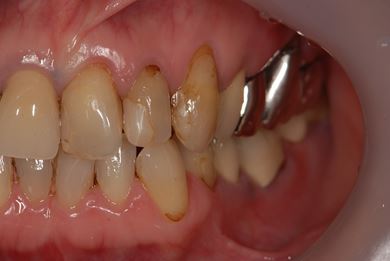

インプラントの症例写真 IMPLANT

骨再生スピードインプラント治療+セラミック治療

| 主訴 | 左上の歯に以前から歯周病があり、多少のぐらつきがあったが、ここにきていよいよ限界になりました。食事に影響があるので、インプラントを視野に、とりあえずは抜歯をと思っています。 | ||||||||||||||||||||||||||||||||

| 治療方針 | サイナスリフトにて上顎洞を拳上し、インプラント治療を可能にする。抜歯と同時にインプラント埋入を行い、治療期間を短縮する。 | ||||||||||||||||||||||||||||||||

| 治療内容 | インプラント9本(抜歯即日スピードインプラント、サイナスリフト)、ハイブリッドセラミッククラウン12本(ハイブリッドセラミック用土台3本) | ||||||||||||||||||||||||||||||||